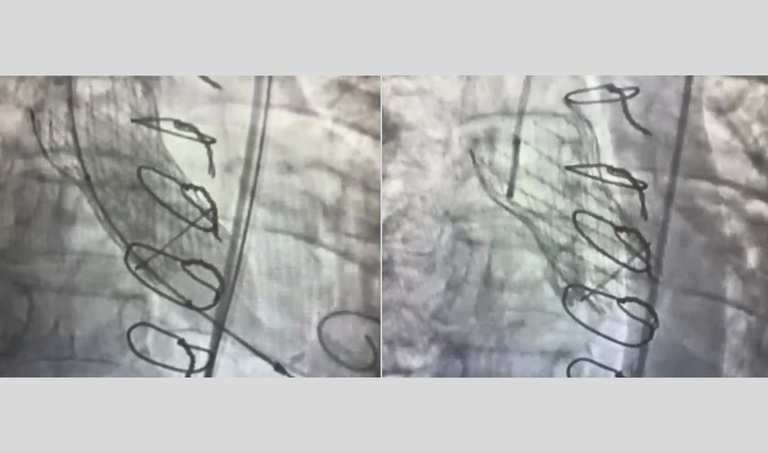

20260317 implante de válvula aórtica imagem 1 - imagens-do-procedimento-video.png

Imagens do implante da válvula aórtica no paciente (captadas a partir de imagem de vídeo).

Curitiba (PR) – O Complexo do Hospital de Clínicas da Universidade Federal do Paraná (CHC-UFPR), vinculado à Empresa Brasileira de Serviços Hospitalares (Ebserh), realizou por meio da Unidade de Cardiologia, Cirurgia Cardiovascular e Cirurgia Torácica, seu primeiro implante transcateter de válvula aórtica (TAVI) sobre uma prótese biológica já existente em um paciente. O processo é denominado Valve-in-Valve.

A prótese biológica previamente implantada no paciente de 77 anos evoluiu com desgaste e apresentava insuficiência ao longo do tempo. A estratégia terapêutica para esse paciente foi o implante de uma nova prótese valvar por meio do TAVI. A funcionalidade do dispositivo é permitir a saída do sangue no coração e impedir seu retorno para o interior deste órgão.

De acordo com o médico do serviço de Hemodinâmica e Cardiologia Intervencionista do CHC-UFPR, Pedro Nicz, o procedimento, conduzido com sucesso pela equipe da Hemodinâmica, representa um marco institucional e um importante avanço assistencial, científico e tecnológico para o CHC-UFPR. “Tivemos um excelente resultado técnico e clínico. Isso permitiu o tratamento do paciente que estava muito sintomático”, disse Nicz.

Conforme o médico, alguns pacientes que já foram submetidos ao tratamento da doença da válvula aórtica e, em algum momento, tiveram essa válvula trocada por uma prótese biológica, podem apresentar, com o passar dos anos, desgaste nesse dispositivo. “É comum acontecerem falhas nessa prótese, prejudicando sua funcionalidade”, explica o médico. Segundo ele, quando isso acontece, o tratamento bem estabelecido, que pode ser feito por cateterismo, é o TAVI na prótese biológica.

O médico acrescentou que esse procedimento é mais complexo do que o TAVI habitual. “Ao inserir a prótese, às vezes o orifício onde ela deve passar fica apertado. Por isso, solicitamos ao hospital a compra de um balão utilizado para quebrar o anel da prótese já existente e permitir que a nova fique lá dentro, funcionando bem. Com isso, esse procedimento foi realizado com sucesso”, explicou.